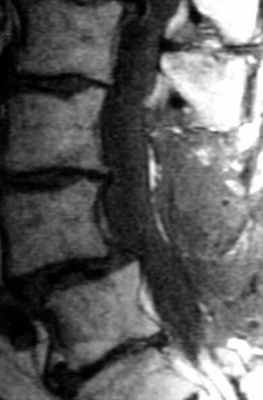

МРТ поясничного отдела позвоночника. Т2-взвешенная сагиттальная МРТ. Стеноз позвоночного канала.

Оценка состояния поясничного отдела позвоночника после операции составляет важную и сложную задачу. МРТ СПб позволяет выбирать место обследования после операции. От правильной трактовки выявленных изменений зависит выбор дальнейшей тактики лечения пациента. Современный взгляд на проблему может быть назван «междисциплинарным», так как требует кооперации специалистов разного профиля: спинальных хирургов (нейрохирургов), лучевых диагностов, специалистов-реабилитологов (физиотерапевтов и т.д.).